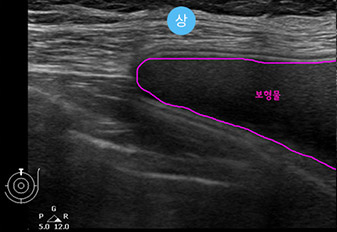

* This is an actual breast ultrasound examination screen after

breast augmentation surgery at View Plastic Surgery. *